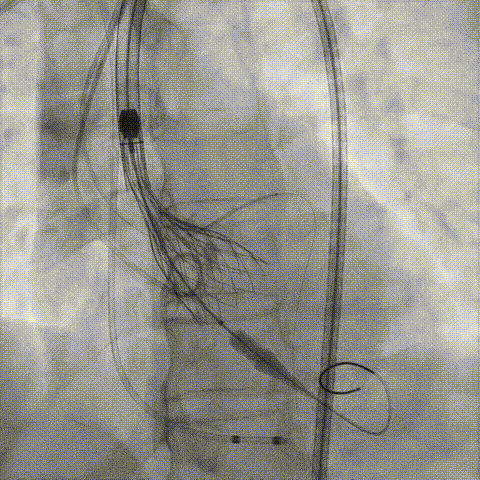

预置Telescope™导引延长导管及导丝保护左冠,

18mm球囊预扩张再次评估冠脉闭塞风险。

Telescope™+Runthrough

18mm*40mm 预扩张

预埋 Resolute Integrity 3.5*26mm

再次评估左冠开口

第一次释放

再次评估左冠开口,考虑调整瓣膜深度